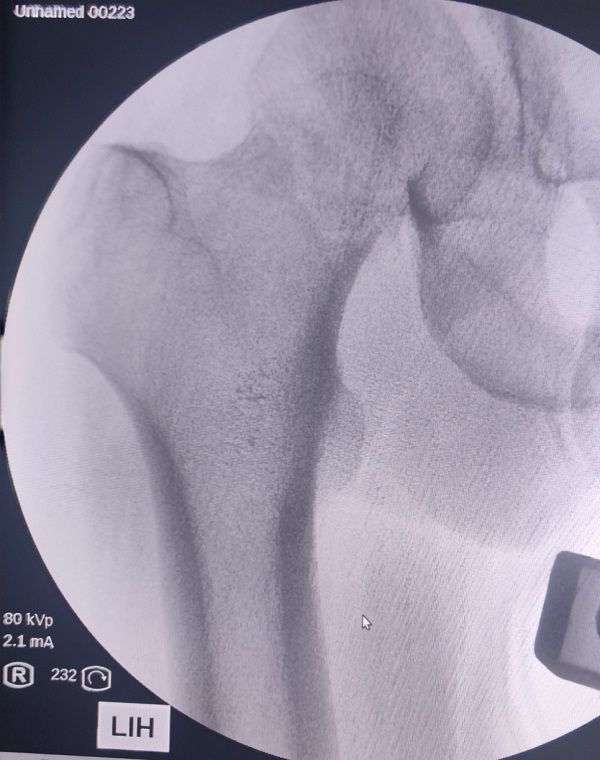

牵引床下复位效果:

术后即刻效果: